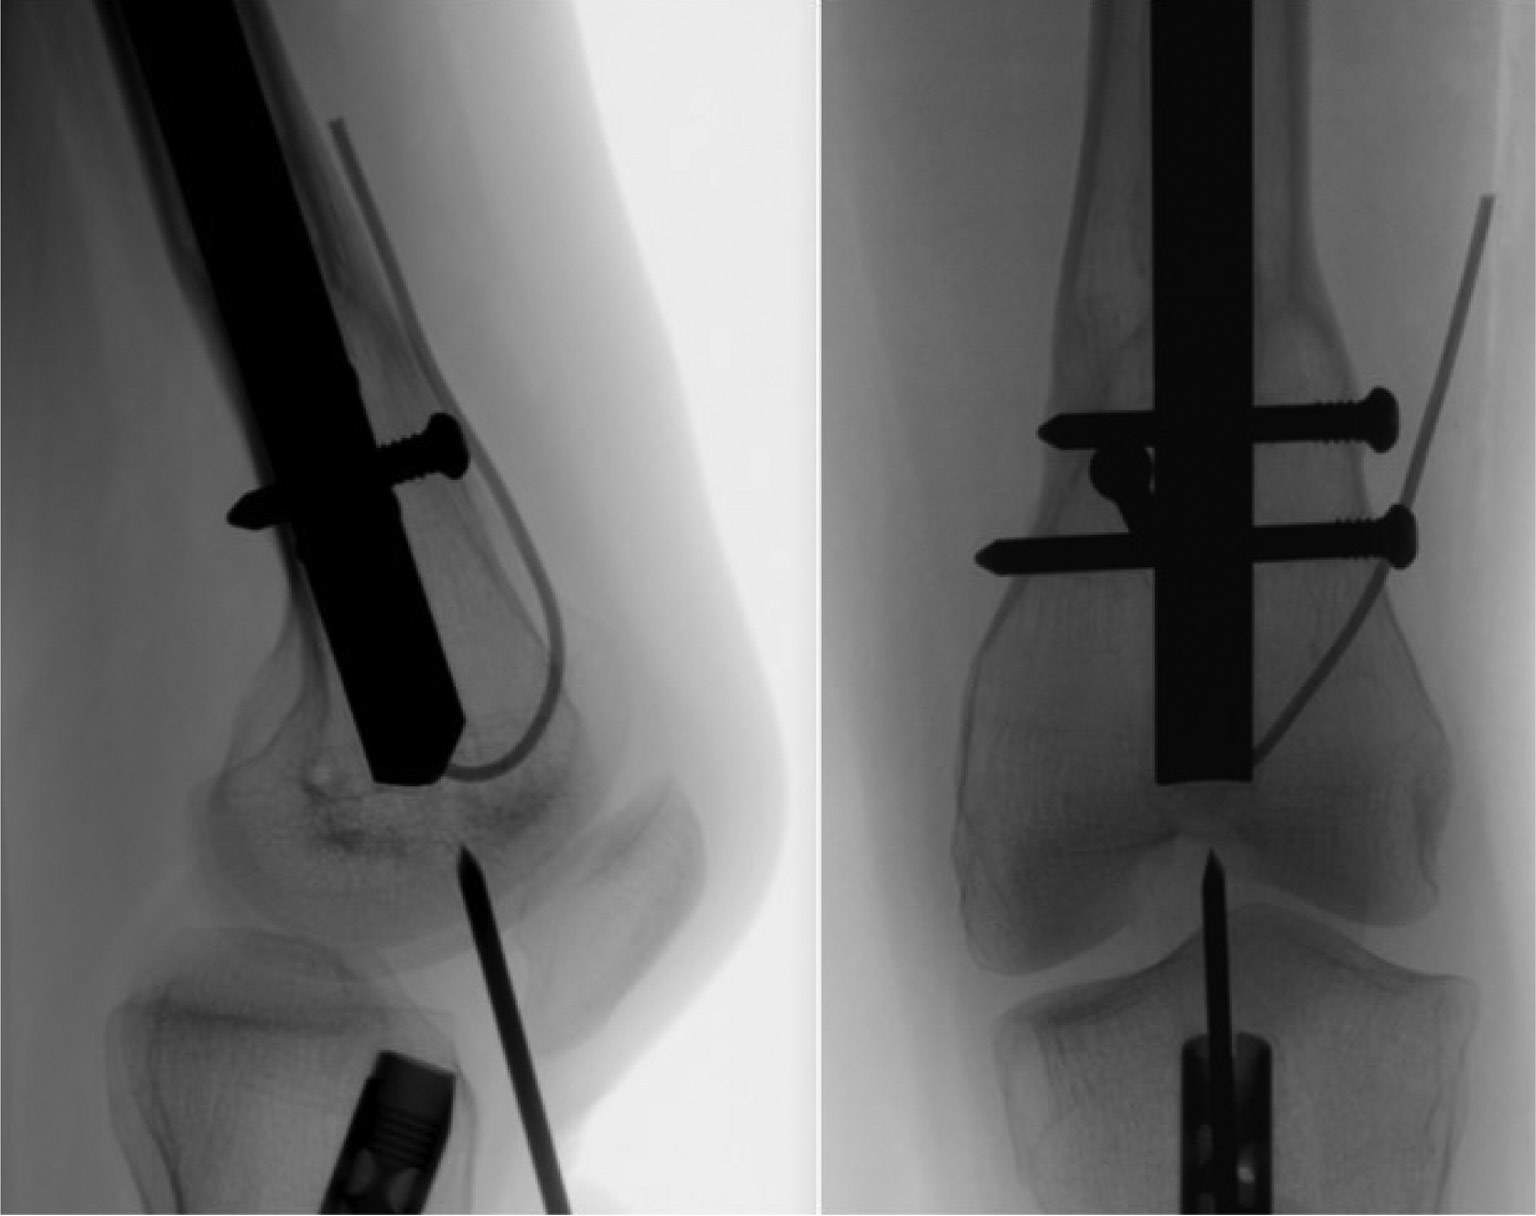

After the proximal interlocking pegs/screws are removed, the distal end of the nail needs to be captured. Similar to antegrade nail, it is important to capture the nail with the retrieval device prior to removing the distal interlocking pegs/screws. The pegs/screws keep the nail locked in position, so it doesn’t rotate or move while tightening the retrieval device into the distal threads of the nail. A sterile triangle or large towel bump should be used to flex the knee approximately 60 degrees. Key Tip: depending on the patella configuration, such as patella baja, the ideal working angle may be different, and the knee flexion should be adjusted to a smaller bending angle by adding a square pillow under the heel. The goal is to find a straight, continuous line to the nail where the patella is out of the path.

Using the original surgical incision for nail insertion, a standard knee arthrotomy approach is made either through or around the patellar tendon. A guidewire is then inserted into the center of the nail in both the anteroposterior and lateral views under fluoroscopic guidance. Key Tip: For retrograde nail removal, a protective tube/sleeve is needed to prevent damage to the cartilage surfaces of the patella when reaming the bone over the nail. A cannulated reamer is used to remove any bone that may be covering the distal end of the nail. The reamer should be at least 1 mm larger than the diameter of the nail. When removing the reamer, be careful not to pull the guidewire out of the nail. A cannulated nail retrieval device can then be passed over the guidewire and used to capture the threads in the distal part of the nail. Use fluoroscopy to assist lining up the retrieval device perfectly parallel to the nail in both the anteroposterior and lateral views before trying to capture the nail threads.

Figure 24. It is important that the guidewire is aligned perfectly to the center of the nail under fluoroscopy in both the coronal and sagittal planes.

jposna20220031_fig24.jpg